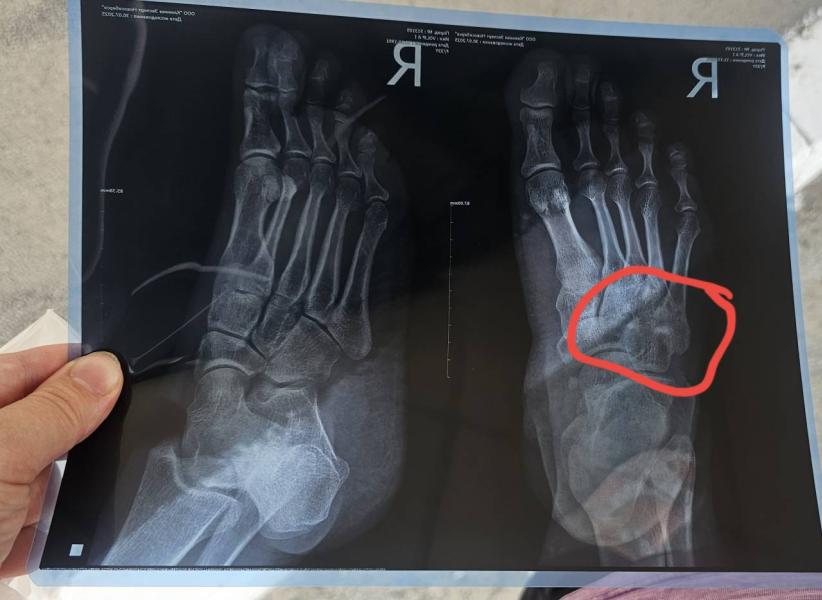

Болит в этом месте нога года 3 , хирург отправил на рентген. 2 белые точки,что могут означать ? Или ничего они не означают, кто понимает? Только 10го на прием

Спасибо, большое . Вот у меня ступня и болит , только отдает в это место где обвела. Последние время за рулём больно ездить , газ тормоз нажимаю и искры из глаз . Щас резко прошло , отголоски только . И так по гругу